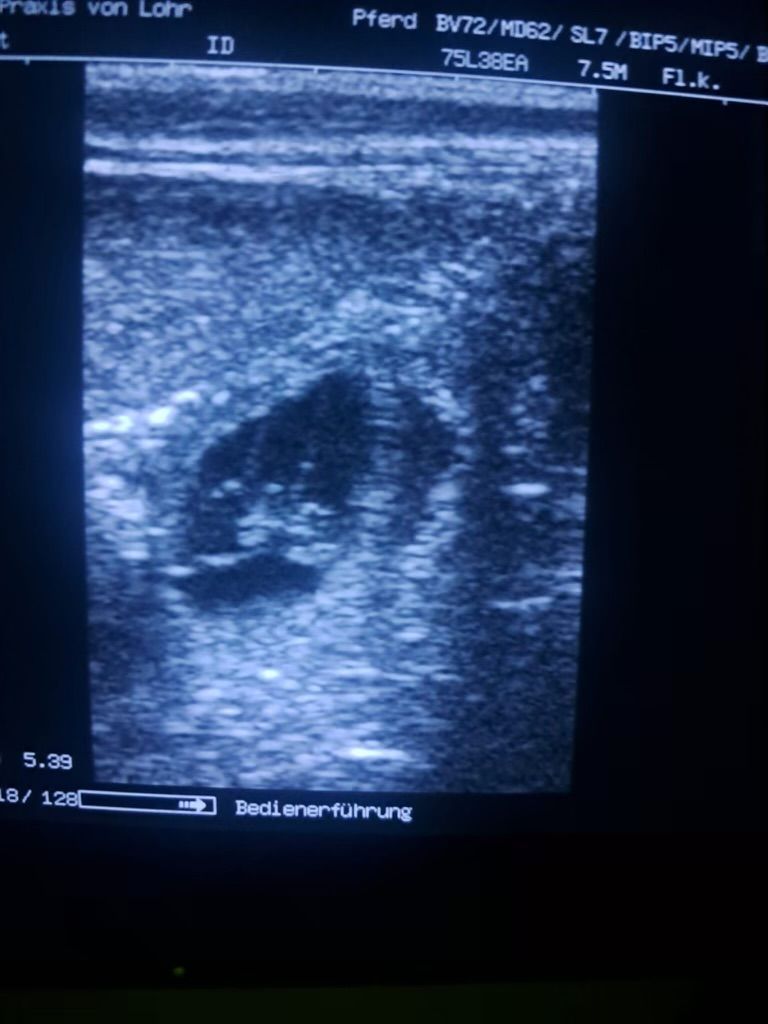

Riley ist schwanger

Nun ist es bestätigt und es ist sicher

Riley ist tragend und die Welpen werden Anfang April erwartet.